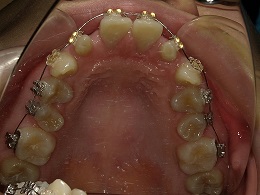

治療前上顎

治療中上顎

治療後上顎

お試し矯正後、深い噛み合わせ改善のため上下全体矯正中の患者様の症例になります。